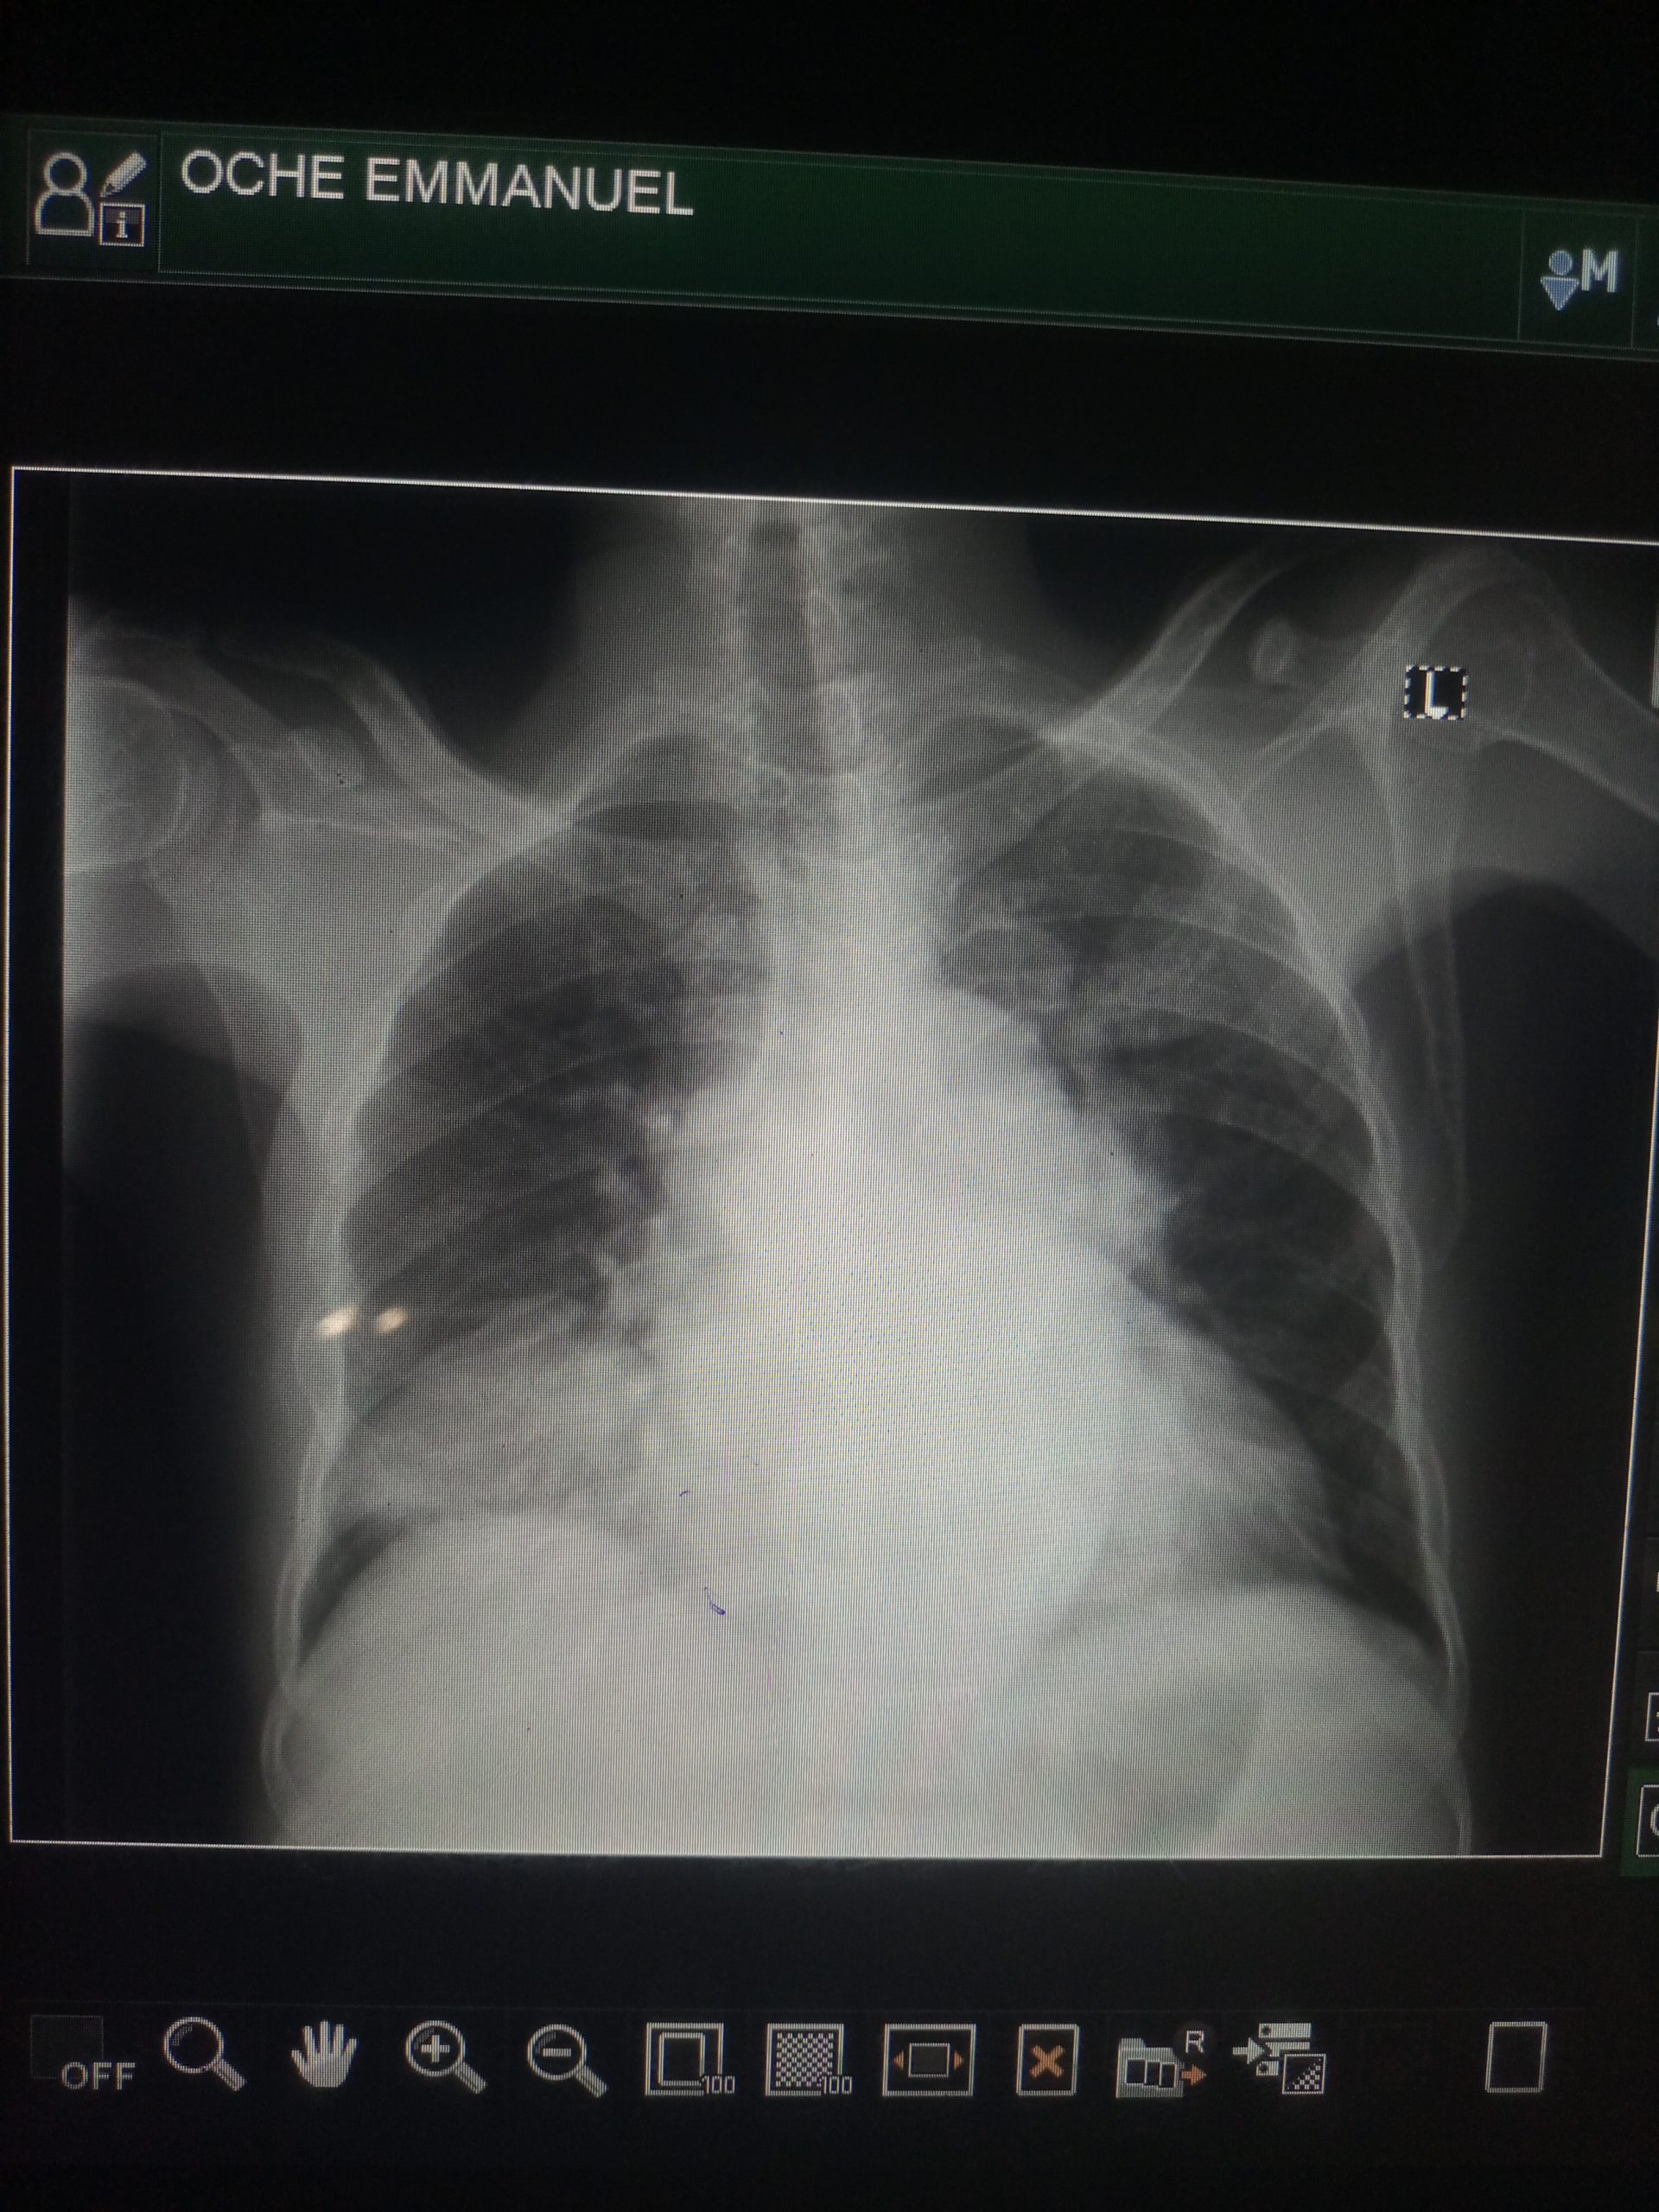

Save Oche Emmanuel from Heart ❤️ failure

Makurdi, Nigeria